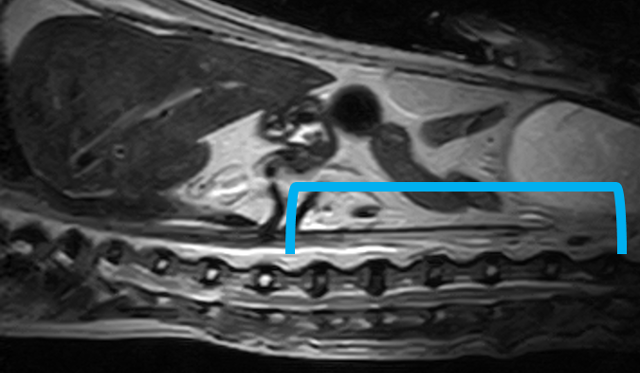

W obrębie kanału kręgowego najczęstszymi wskazaniami do badania rezonansem magnetycznym u zwierząt są:

• ocena przepukliny i stopnia ucisku na rdzeń kręgowy

• dyskopatie, neuropatie, radikulopatie

• urazy kręgosłupa

• zwyrodnieniowe zwężenie lędźwiowe krzyżowe (DLSS)